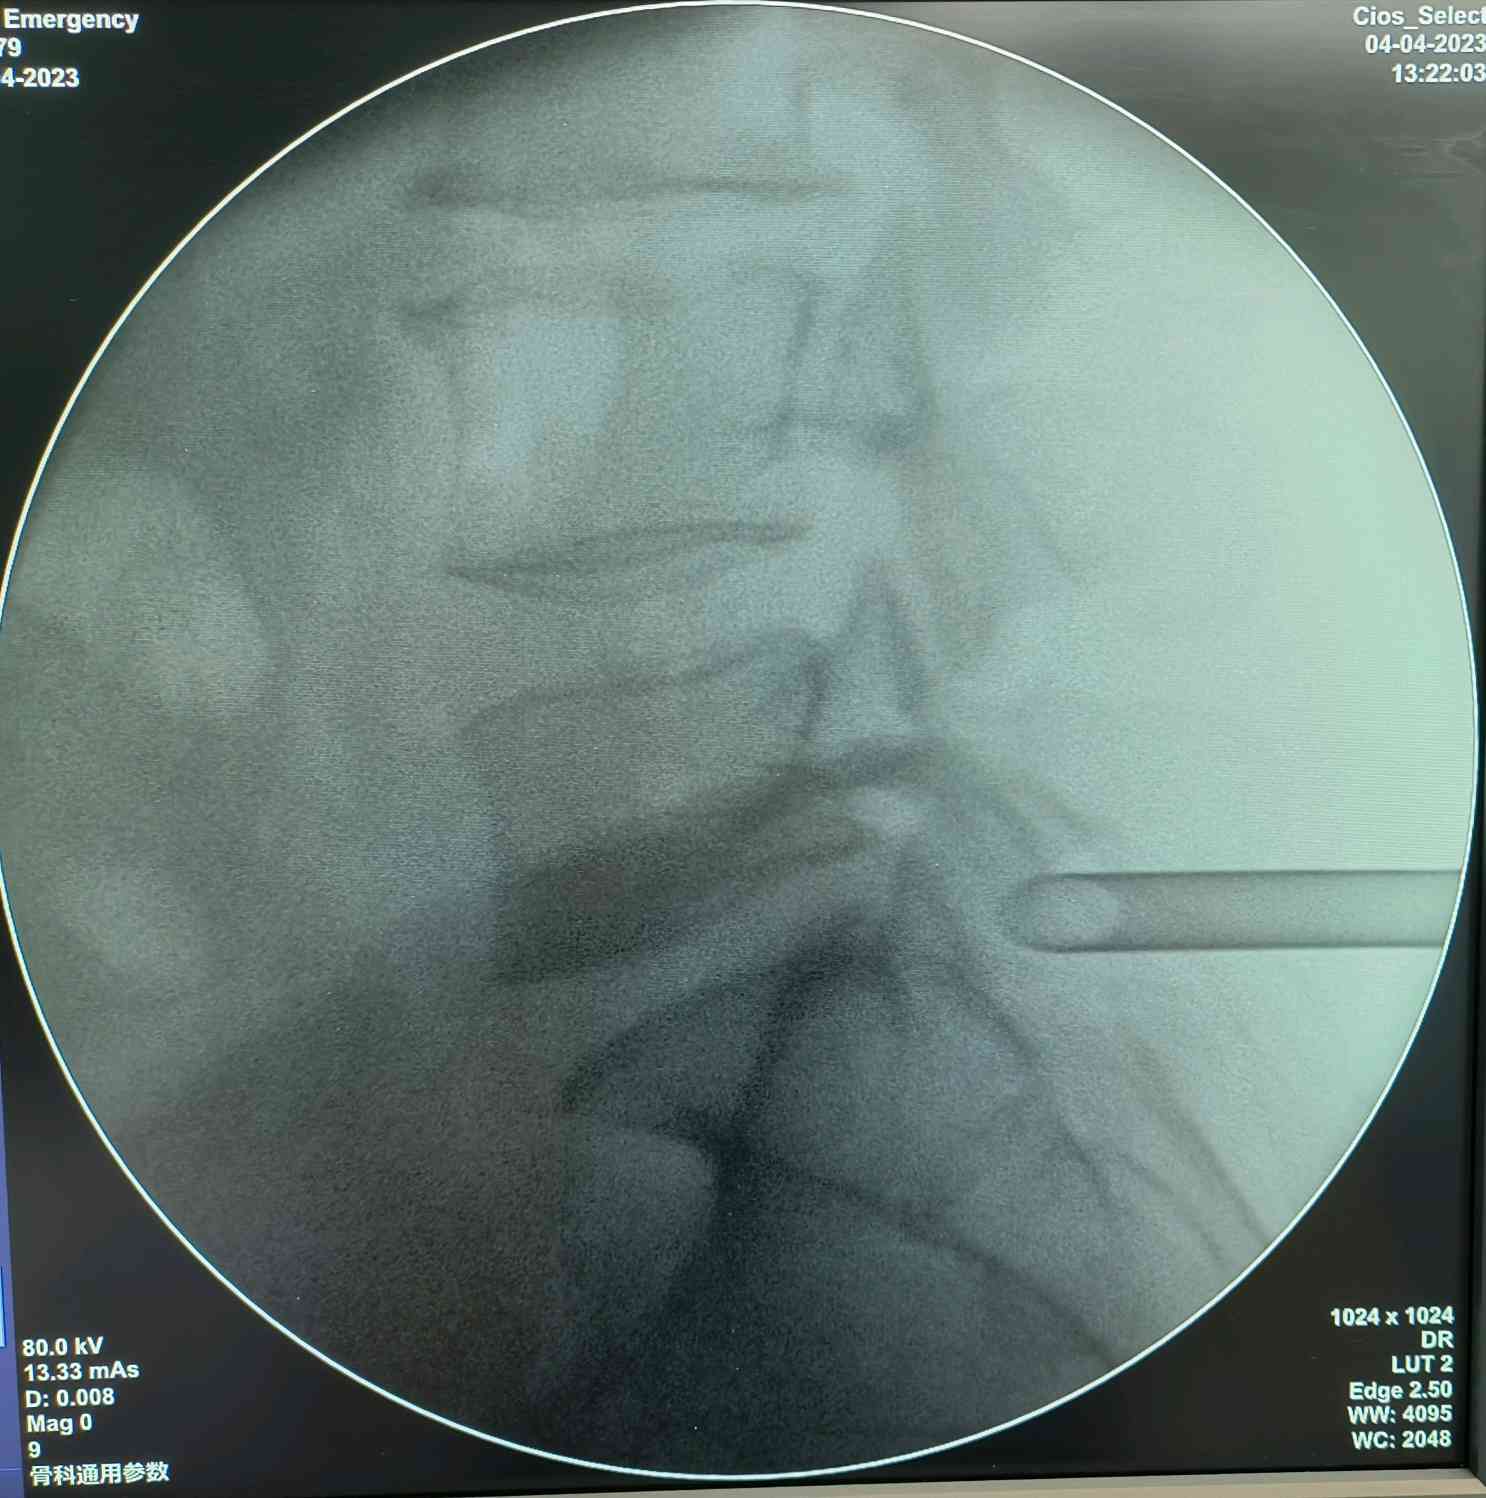

一个0.7cm大小的切口,下一个内镜进去,半个小时,全程无痛,就解决了神经受压,术中即感疼痛消失!

针对破裂的椎间盘,我们可以做一个纤维环缝合,就是把椎间盘的破裂口缝合起来,既保证了椎间盘的正常功能,又可以减少椎间盘突出的复发!

看着椎管内自由的神经根,心情是愉悦的,患者的心情更加愉悦,因为没有了那种钻心的疼痛!